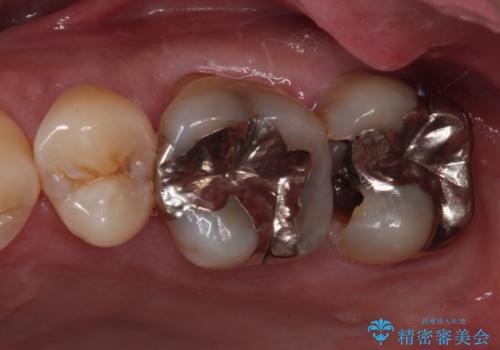

- 酒席の後に転倒して前歯を損傷し、応急処置のみを受けてきたとのことで来院された患者様です。

損傷がひどく、前歯4本と広範囲であったため、症状やレントゲン写真、検査結果が一致せず、定期的に経過を見ながら診断していくこととしました。

右側前歯は歯根が短くなり、パンチング状に歯根に透過像が認められたため、予後不良と判断し抜歯することとしました。

当初のレントゲン写真では根尖部に骨透過像が認められた両サイドの2歯は、歯髄の正常な反応が認められたためそのまま保存し、左側前歯は歯髄が失活していたため根管治療を行うこととしました。

抜歯後の欠損部はブリッジにて補綴治療を行うこととしました。

事故直後のレントゲン写真では全ての歯の根尖部に骨透過像が認められましたが、治療後には全ての透過像がなくなっていました。

診断に2-3ヶ月かかりましたが、的確に診断を行うことができました。